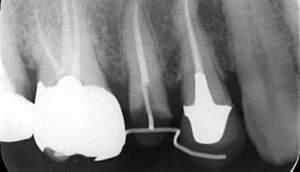

カリエス除去し、MTMを行ったのち、補綴を行う

全体的に10年以上前の治療痕で、銀歯の下でカリエスになっています。今回は右上5に限っての方針を記載する。 |

カリエスを取り除くと、遠心の歯質が歯肉縁下になりました。

MTM開始直後と、終了後です。フックの位置が変わっているのがわかると思いますが、それが歯が動いた証拠となります。

歯からはフック、隣り合った歯にはワイヤーが渡してあります。そこにゴムをひっかけて歯を挺出させます。